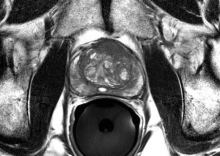

Ronald Wheeler, M.D., along with contributing radiologists, authored a clinical study demonstrating the use of magnetic resonance imaging (MRI) in the diagnosis and treatment of prostate cancer indicating a greater than 99 percent rate of cure when combined with high-intensity focused ultrasound (HIFU) treatment.